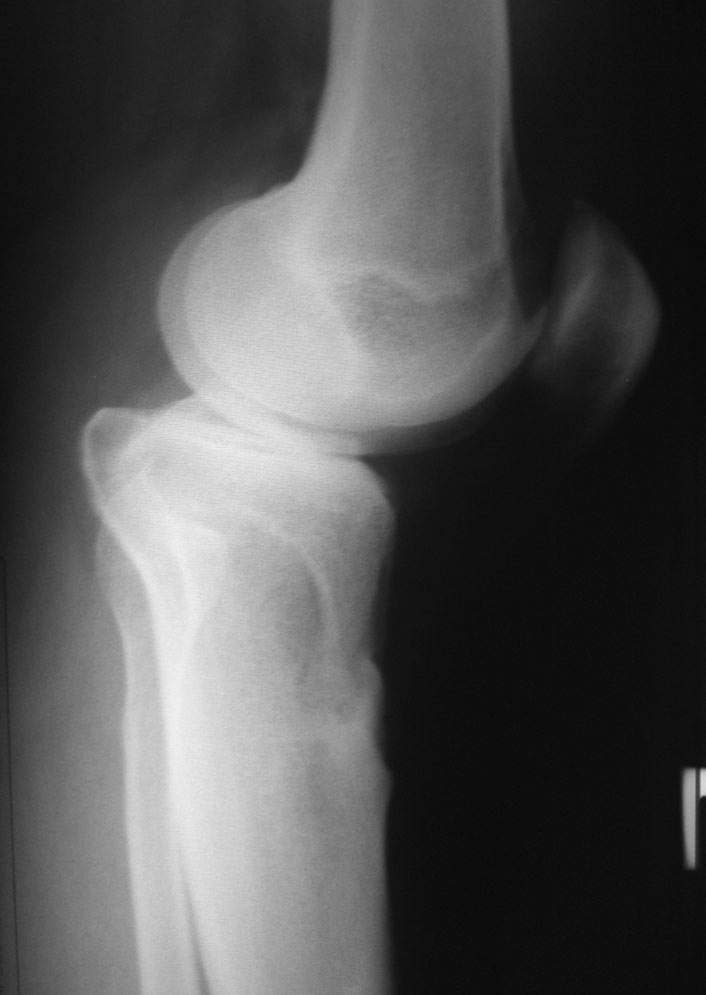

Уважаемый доктор Зайцев! Причина деформации проксимальной тибии у Вашего пациента - преждевременное и несимметричное закрытие зоны роста передней части проксимальной ростковой зоны б/б кости в следствии окультной травмы произошедшей в возрате 10-12 лет. Есть 2 причины рекурвационной деформации в области коленного сустава - мягкотканевая и костная.В данном случае Вы имеете дело не с рукурвацией коленного сустава, а с рекурвационной деформацией проксимальной голени. "Заднего выдвижного положения" на самом деле нет.То, что Вы видите на боковом снимке - это не задний подвывих голени - это снимок, сделанный в сгибании коленного сустава. Дело в том, что костные дефорсации в области коленного хорошо компенсируются за счёт движения в суставе. поэтому то, что вы видите, как задний подвывих на самом деле - сгибательное положение колена.

Это можно проверить очень просто - надо сделать стресс рентгенограмму в положении полного разгибания коленного сустава.Для этого посадите больного на стул, пятку поставьте на другой стул, дайте пациенту кассету 30Х40 держать с наружной стороны колена, и попросить ренгентехника сделать латеральный снимок с втутренней стороны. Сделав снимок здорового колена, Вы сможете расчитать деформацию.

Если величина деформации больше, чем "переразгибание" сустава, то имеется не только деформация проксимальной тибии, но и сгибательная контрактура.